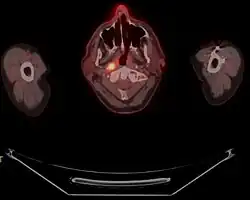

![]() Obraz histologiczny przerzutu raka nosogardła do węzła chłonnego, barwienie H-E | |